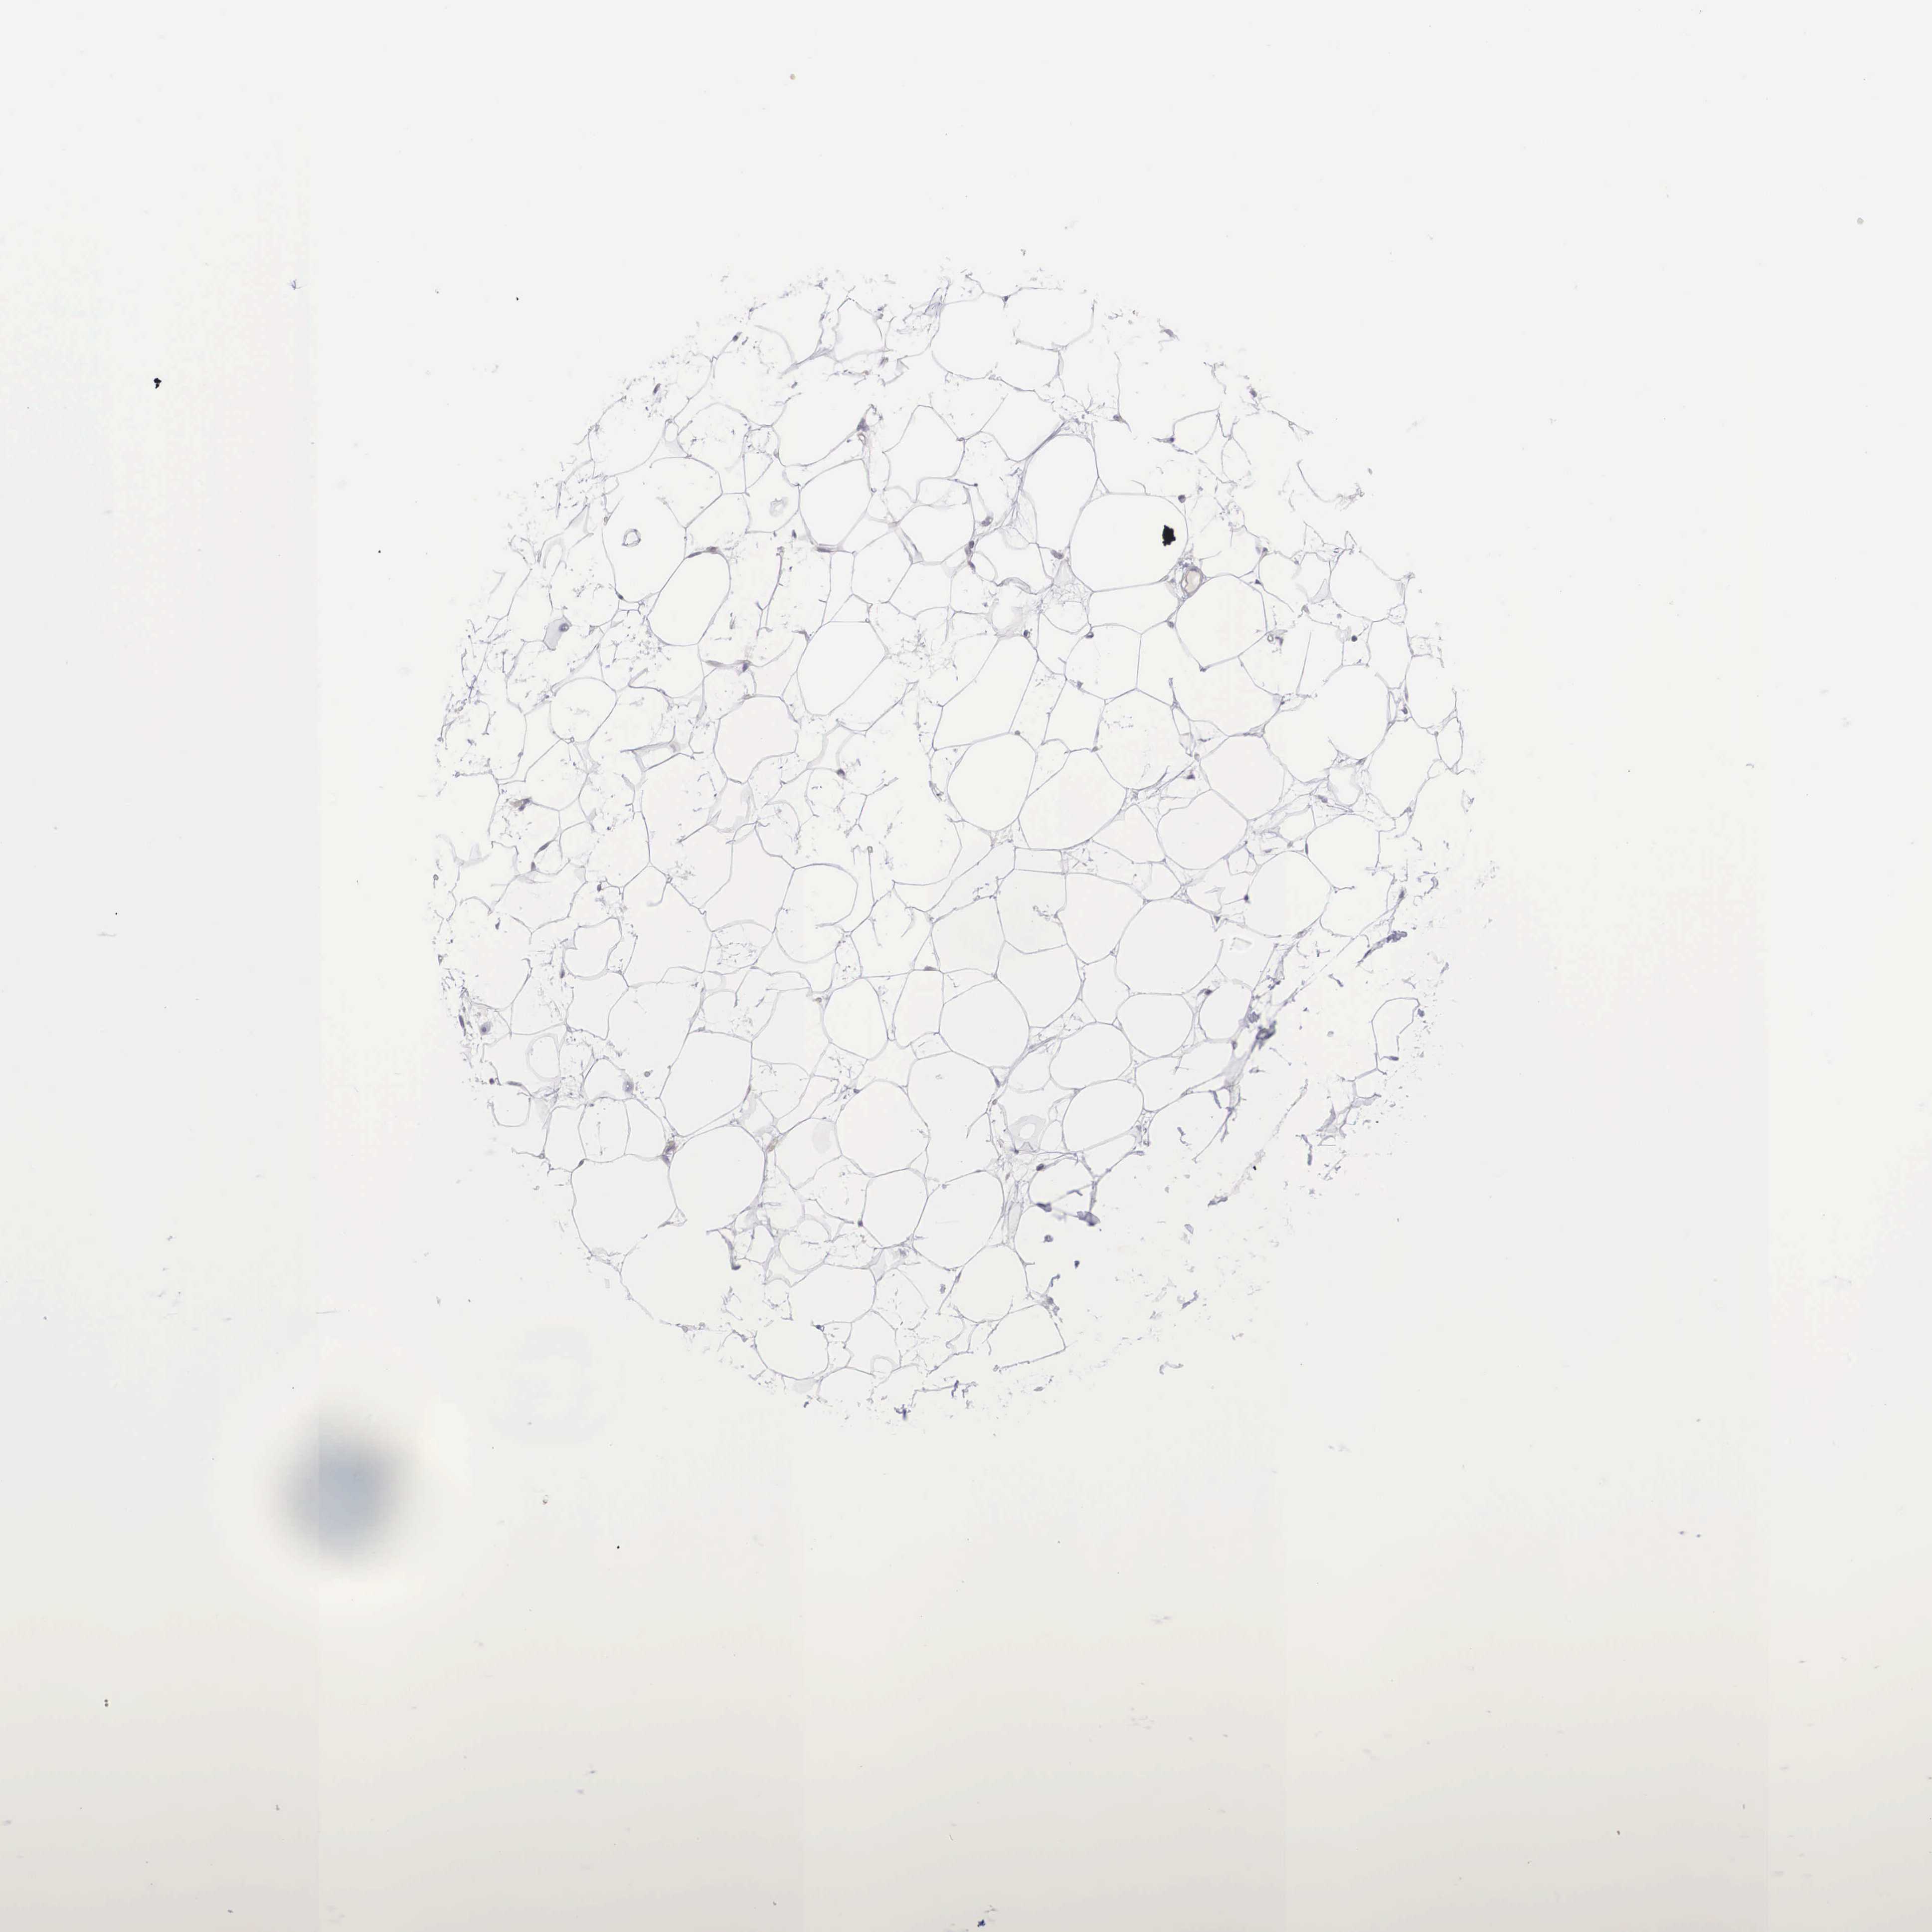

MAST4